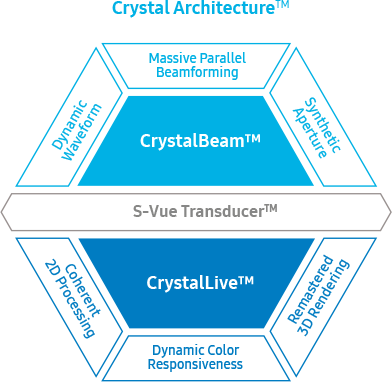

Tehnologii de imagistică redefinite bazate pe

Crystal Architecture

Crystal Architecture

Crystal Architecture este o arhitectură de imagistică care combină CrystalBeam și CrystalLive, bazându-se pe S-Vue Transducer, capabil să ofere o imagine clară. CrystalBeam este o nouă tehnologie de formare a fasciculului utilă pentru a returna rezoluția imaginii de înaltă calitate și o mai mare uniformitate a imaginii. CrystalLive este motorul inovator de imagistică cu ultrasunete de la Samsung, care oferă procesare îmbunătățită a imaginii 2D, randare 3D și semnal de culoare, oferind imagini uimitoare și flux de lucru eficient în cazurile complexe.